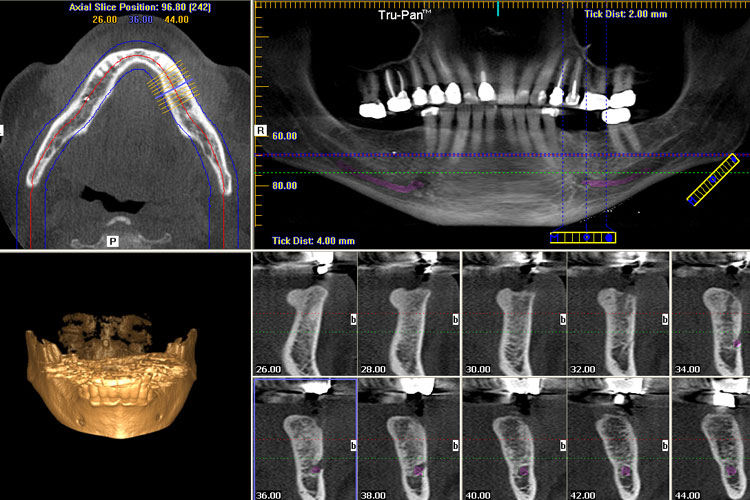

- Diagnostic Acquisition: CBCT scan (0.076-0.12mm voxel) performed at point-of-care with AI-assisted positioning (e.g., Planmeca ProFace+, Carestream CS 9600 AI).

- Surgical/Prosthetic Fusion: DICOM data merged with intraoral scan (IOS) in CAD software. Enables immediate visualization of bone-to-restoration relationships for same-day decisions.

- Guided Surgery Execution: CBCT-derived surgical guide fabricated chairside via 3D printer (e.g., SprintRay Pro 95) within 45 minutes.

- Automated Segmentation: AI-driven tissue separation (bone, nerves, mucosa) using tools like Materialise Mimics Innovation Suite, reducing manual segmentation time by 70%.

- Hybrid Model Generation: CBCT bone structure + IOS soft tissue merged into single virtual model for crown/bridge, denture, or implant cases.

- Biomechanical Simulation: Integration with finite element analysis (FEA) software (e.g., 3Shape FEA Module) for load distribution validation pre-fabrication.